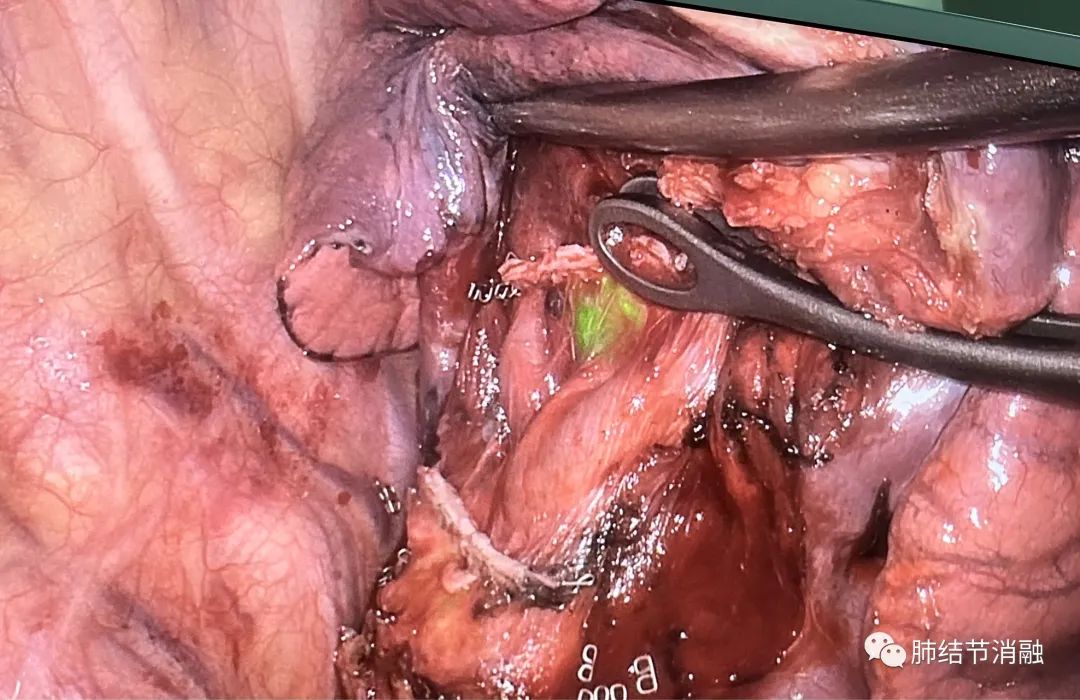

定位后立即展开胸腔镜手术

主病灶染色区域

次要病灶1染色区域

次要病灶2染色区域,气管边上

手术切除8毫米主病灶

次要病灶1 5毫米结节

次要病灶2 3毫米结节